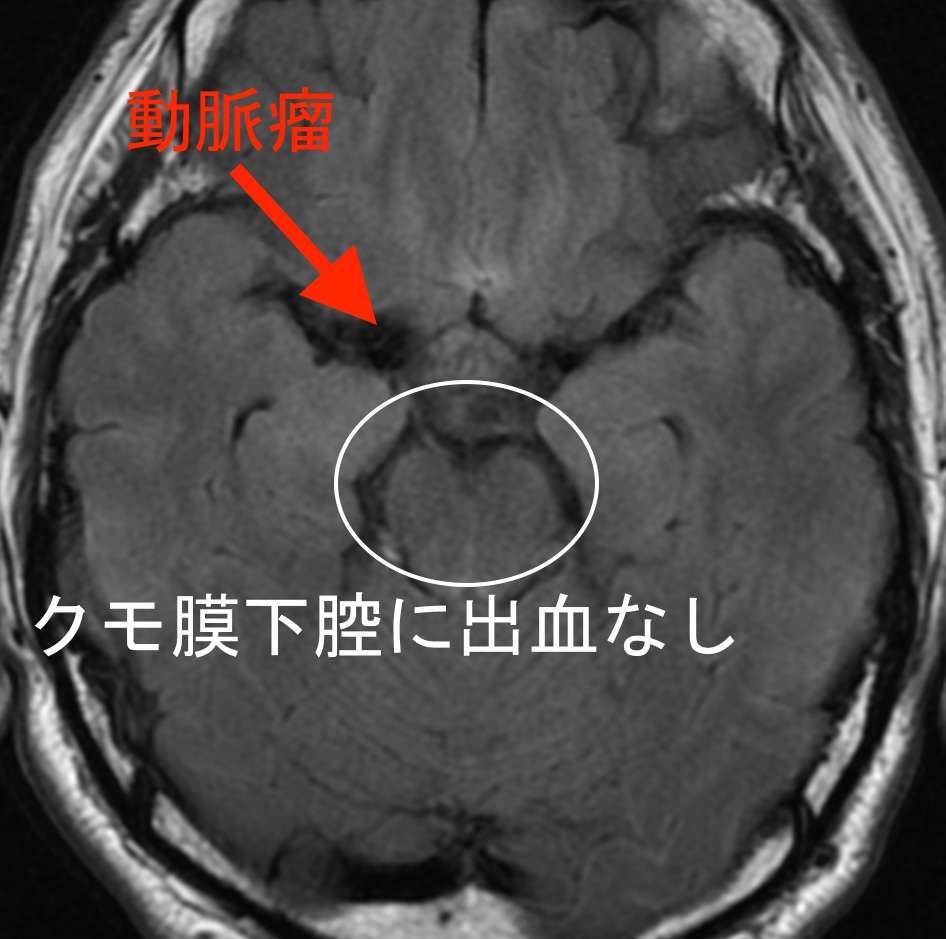

MRAで、右中大脳動脈に直径約5cmの巨大脳動脈瘤が見つかりました。破裂した場合、くも膜下出血を起こす危険があります。

しかし、頭部の断層画像では、出血した形跡はありませんでした。